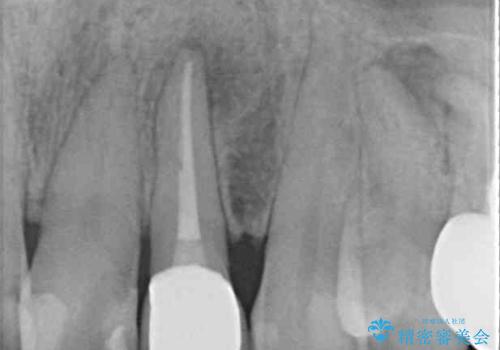

レントゲン写真から、大きくなった根尖病変が認められました。

根管治療後速やかに痛みが消退し、6ヶ月後のレントゲン写真では、根尖部の病変がほぼなくなっていることが分かりました。